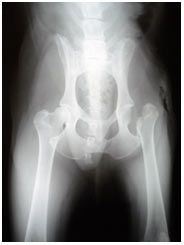

2.Operasi (Femoral Head Ostectomy)

Operasi pemotongan kepala tulang Femur ini hanya dilakukan pada anjing yang beratnya kurang dari 30 kg dan hewan tersebut betul-betul kesakitan bila menggunakan kakinya. Operasi sebaiknya dillakukan oleh dokter hewan yang sudah mempunyai pengalaman cukup untuk melakukan operasi ini, karena resikonya sangat besar.

Gambar. Gambaran radiologi ventrodorsal persendian pinggul pasca operasi Femoral Head Ostectomy (operasi dilakukan tahun 2007).